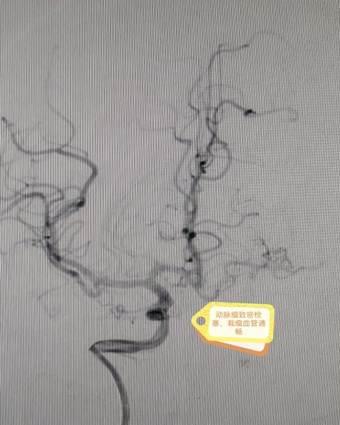

在麻醉科、手术室等多科室通力配合下,丁昊主任团队凭借丰富的经验与精湛的技术,顺利完成两阶段高难度手术。术后,李阿姨恢复良好,未出现神经功能损伤,脑血流显著改善,动脉瘤成功隔绝。护理团队全程实施个性化康复计划,从病情观察到心理疏导,从功能锻炼到生活护理,以专业与温情助力患者快速康复。

4e0f58a2851175c25ba8553546c65de  e18d0216cc52e38d359a4be9fc10ef1

术后DSA结果